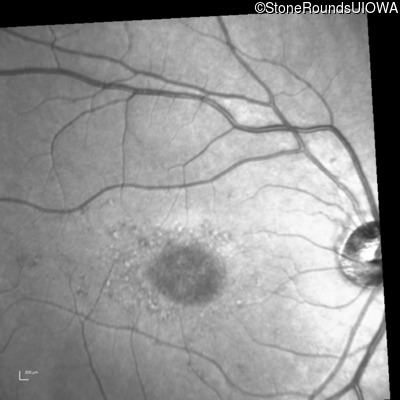

Infrared Fundus Photograph - Left - 20/80

Exemplar